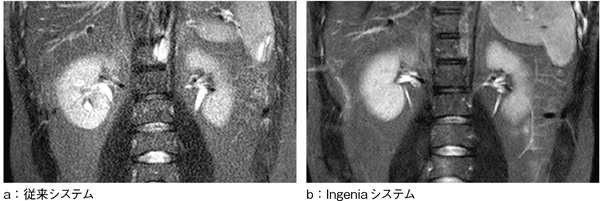

これらRF受信プロセスのデジタル化,簡素化は,システムの半永久的な拡張能力と同時に,画質の向上にも大きく寄与する。アナログケーブルの距離が長くなれば,信号ロスが起こる。コイルが多チャンネル化されると,各コイルにつながっているワイヤーを束ねて配線するために,クロストークも増加する。しかも,従来のアナログ回路では,コイルの多チャンネル化に伴う回路の拡張を簡素化するために,複数のアナログ信号同士を多重化(multiplexing)することでADCの数を減らすという技術が用いられている。図1 a,bでは,その典型例を示している。2チャンネル受信回路(図1 a)では4つのADCが用いられているが,複数チャンネル受信回路(図1 b)では3つのADCしか用いられていない。このような処理は,せっかくの多チャンネル化のパフォーマンスを低下させ,SNRの低下,画質の劣化へとつながる。一方,信号受信直後,各コイルで受信した信号ごとにダイレクトにデジタル変換を行うdStreamでは,そのような劣化原因をすべて除くことができる。その結果,画像のSNRを従来システム比で最大40%増加させることに成功した。図3に,従来システムとIngeniaシステムそれぞれで撮像された腹部画像の比較を示しているが,まったく同じ条件での撮像でありながら,SNRに大きな差があることがわかる。

図3 dStreamを用いたSNRの上昇